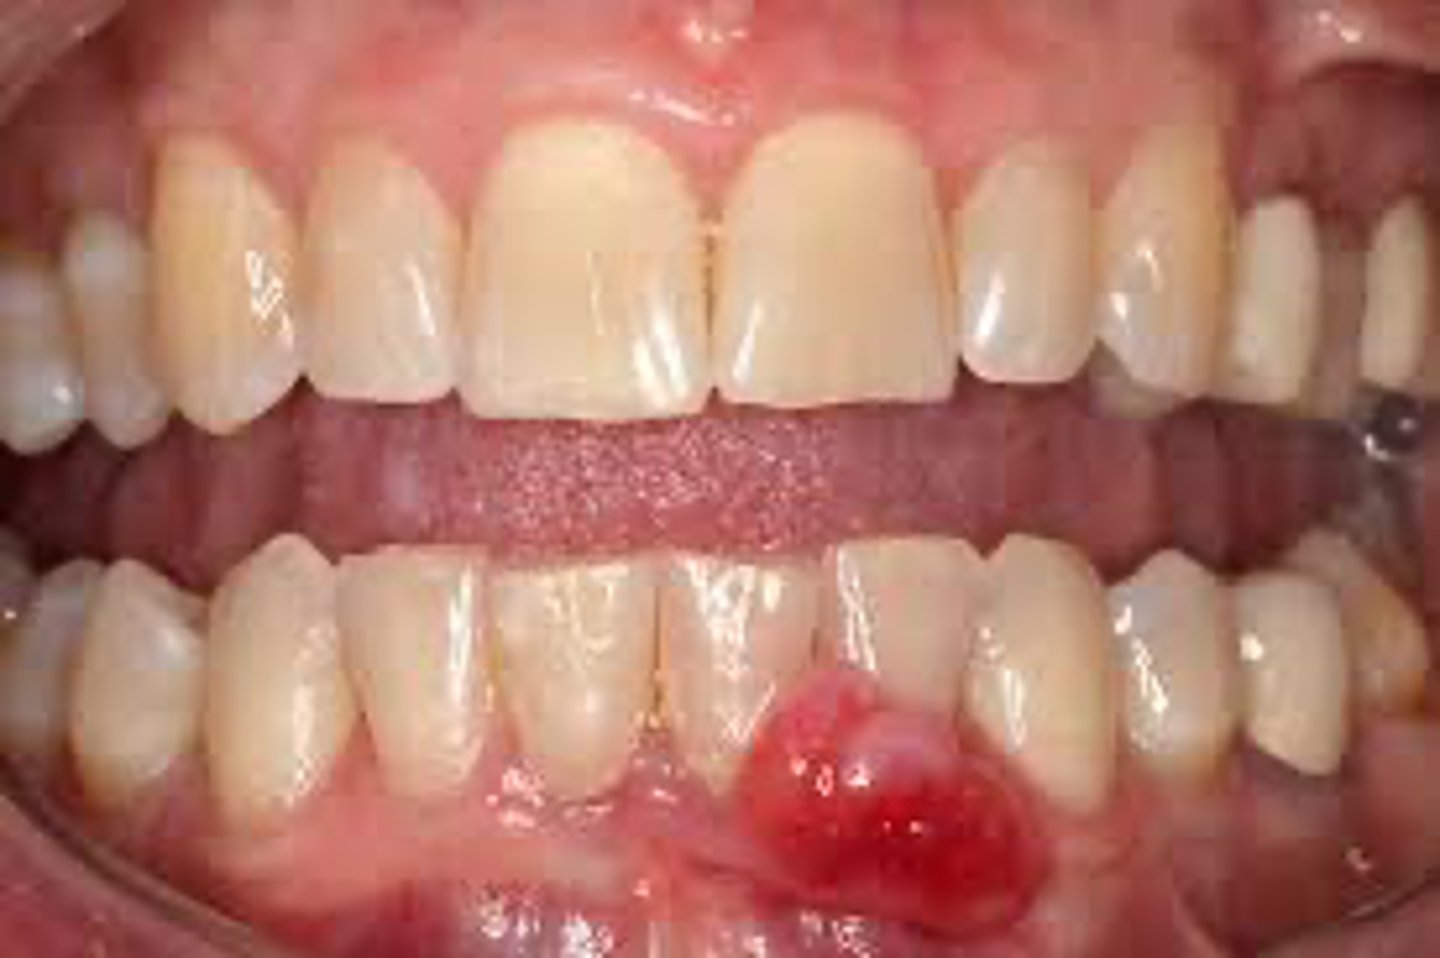

A lesion is described as a benign, solitary vascular growth that represents an exuberant tissue response to local irritation or trauma.

pyogenic granuloma

A patient presents with a pyogenic granuloma on the gingiva. What is the most appropriate treatment?

surgical excision and removal of local irritants

Which of the following is NOT a characteristic of pyogenic granuloma?

contains purulent exudate